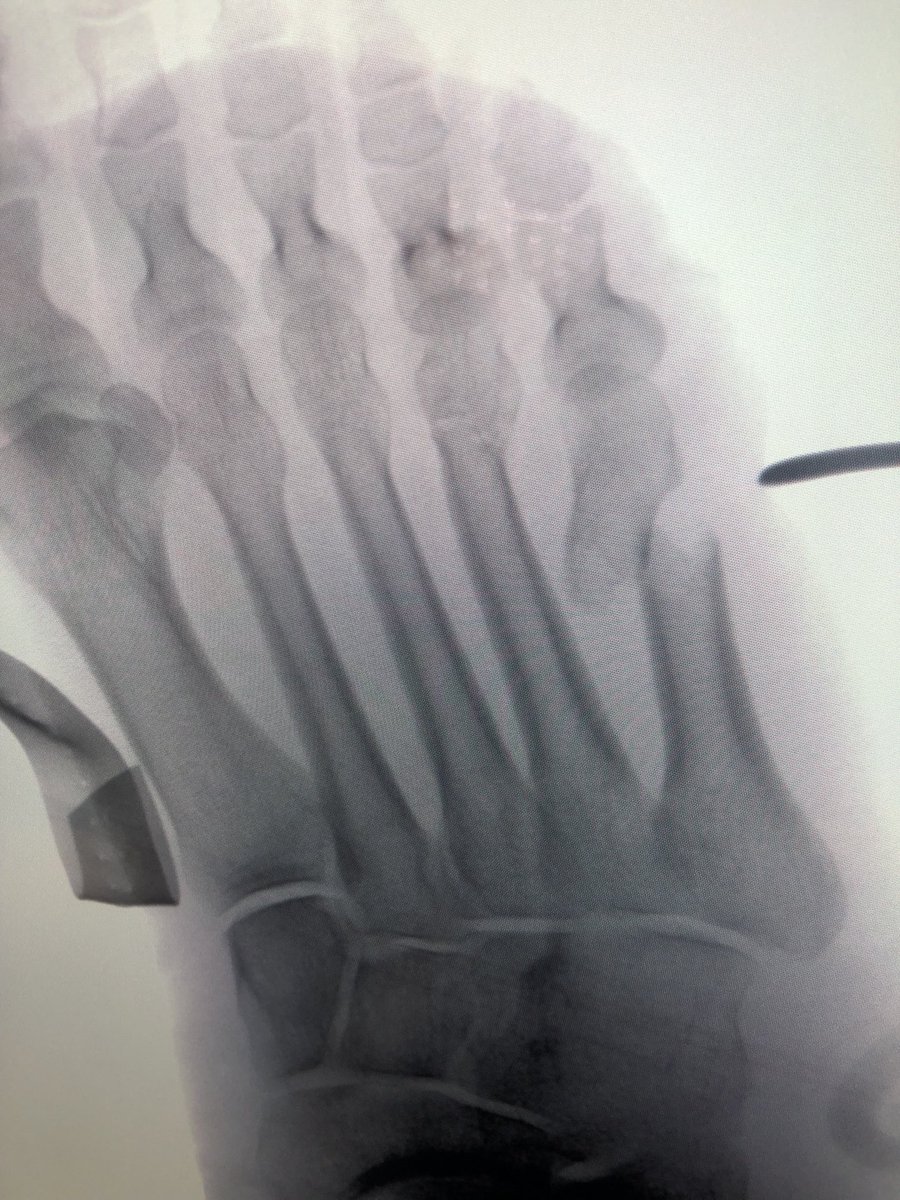

🔎CASE IN FOCUS! 🩻 How would you treat this fracture in a fit and active 73-year-old male patient five years after a well-functioning primary THA? a) Revision - cement in cement b) Revision - uncemented fluted taper c) Fixation - PPF locking plate d) Fixation - DCP #THA #BJJ

How would you treat this #periprosthetic #fracture #orthotwitter?